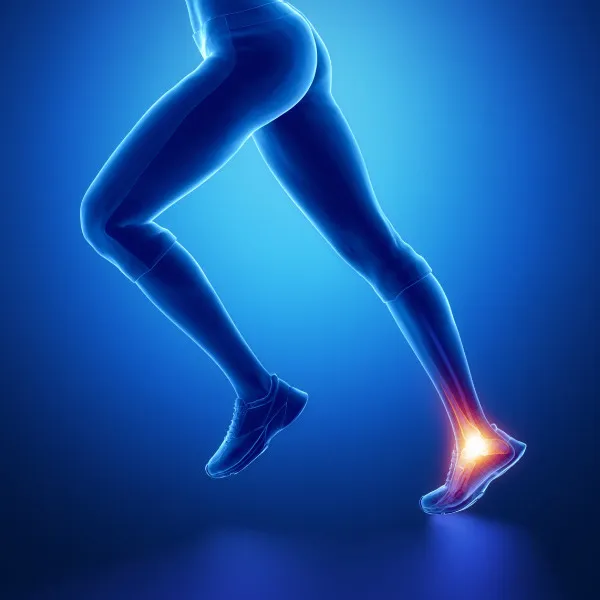

Сложный сустав, обеспечивающий опорную и двигательную функцию. Работаем с травмами связок, сухожилий, переломами лодыжек, воспалительными заболеваниями и хроническими болевыми синдромами.